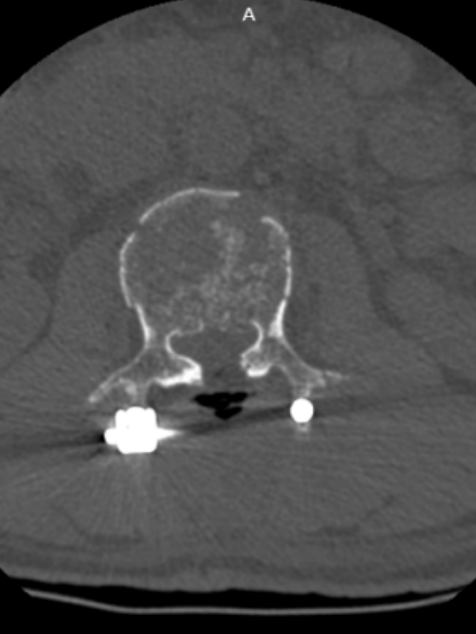

椎管压迫仅剩5毫米!骨科团队“精雕”碎骨,成功解除瘫痪危机

此次手术的成功实施,标志着对宋先生严重脊柱创伤的关键性胜利。绍兴袍江医院骨科团队在狭窄的空间内,精准完成了椎管减压、神经修复、脊柱复位与固定等一系列复杂操作,有效解除了脊髓压迫危机,重建了脊柱的力学结构。